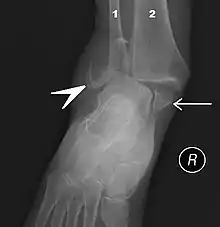

Ankle fractures may result from excessive stress on the joint such as from rolling an ankle or from blunt trauma.[20][21] Types of ankle fractures include lateral malleolus, medial malleolus, posterior malleolus, bimalleolar, and trimalleolar fractures.[20] The Ottawa ankle rule can help determine the need for X-rays.[21] Special X-ray views called stress views help determine whether an ankle fracture is unstable.

The initial evaluation of suspected ankle pathology is usually by projectional radiography ("X-ray").

For ligamentous injury, there are three main landmarks on X-rays: The first is the tibiofibular clear space, the horizontal distance from the lateral border of the posterior tibial malleolus to the medial border of the fibula, with greater than 5 mm being abnormal. The second is tibiofibular overlap, the horizontal distance between the medial border of the fibula and the lateral border of the anterior tibial prominence, with less than 10 mm being abnormal. The final measurement is the medial clear space, the distance between the lateral aspect of the medial malleolus and the medial border of the talus at the level of the talar dome, with a measurement greater than 4 mm being abnormal. Loss of any of these normal anatomic spaces can indirectly reflect ligamentous injury or occult fracture, and can be followed by MRI or CT.[25]